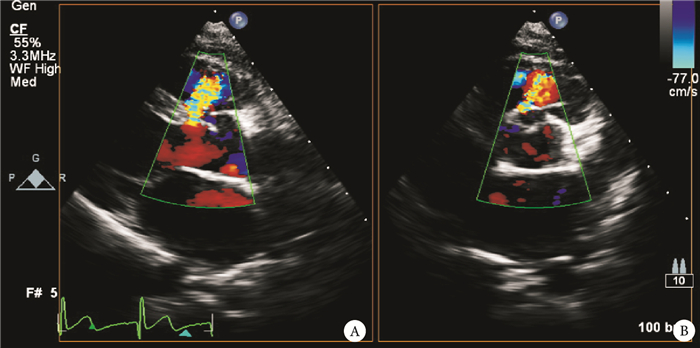

對于擬行雙動脈干下室間隔缺損經胸封堵術的患者,全面的術前影像學評估及完善的手術策略制定是保證成功關鍵。經胸超聲心動圖是最常用也是最為重要的術前檢查評估手段,其能清晰地顯示室間隔缺損的大小,分流程度,主動脈瓣膜的形態及功能,缺損與肺動脈瓣之間的距離等重要指標(圖 1)。術前經胸超聲心動圖評估內容應包括:(1)室間隔缺損的大小(包括長軸徑及短軸徑),或者其三維輪廓;(2)主動脈瓣膜形態及功能,是否合并瓣膜脫垂,是否存在主動脈瓣膜反流;(3)心臟功能,各心腔大小及心內分流量(估測Qp/Qs)。術中可采用經食管超聲心動圖(trans-esophageal echocardiogram,TEE)對室間隔缺損進一步評估,相對于經胸超聲心動圖,TEE能夠提供更為全面的解剖信息,TEE評價的切面包括食管中段五腔心平面,主動脈短軸平面及左心室長軸平面,這樣可以較為準確地測量缺損的大小。同時TEE也可以清晰地顯示主動脈瓣膜的形態與功能,判斷是否存在脫垂,而同時該切面也是引導心內操作的最佳切面,因為該切面可以同時顯示缺損、主動脈瓣膜及重要心內結構(二尖瓣及其瓣下腱索),也能顯示整個封堵器輸送裝置。如在雜交手術室進行手術或懷疑患者存在肺動脈高壓,也可以運用經導管檢查,明確肺動脈阻力指數,Qp/Qs等指標,并對室間隔缺損的大小、瓣膜脫垂情況進行進一步評估。

圖1

術前經胸超聲及造影評價干下型室間隔缺損

注:超聲清晰顯示室間隔缺損在左心室長軸及短軸切面直徑,以及缺損與主動脈瓣及肺動脈瓣膜的關系(緊臨主動脈瓣膜及肺動脈瓣膜);A、B:術前造影顯示室間隔缺損位于主動脈瓣及肺動脈瓣下;LV:左心室;Ao:主動脈;LA:左心房;RA:右心房;PA:肺動脈;箭頭所示為室間隔缺損